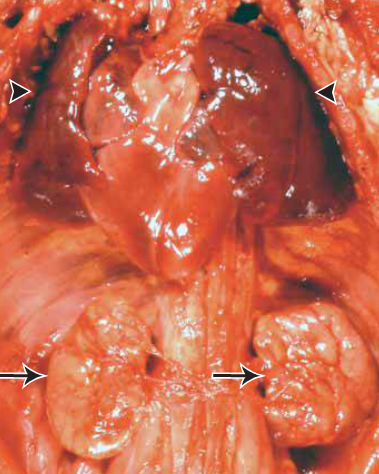

Potter sequence: pulm hypoplasia and what shown in pic

bilat renal agenesis